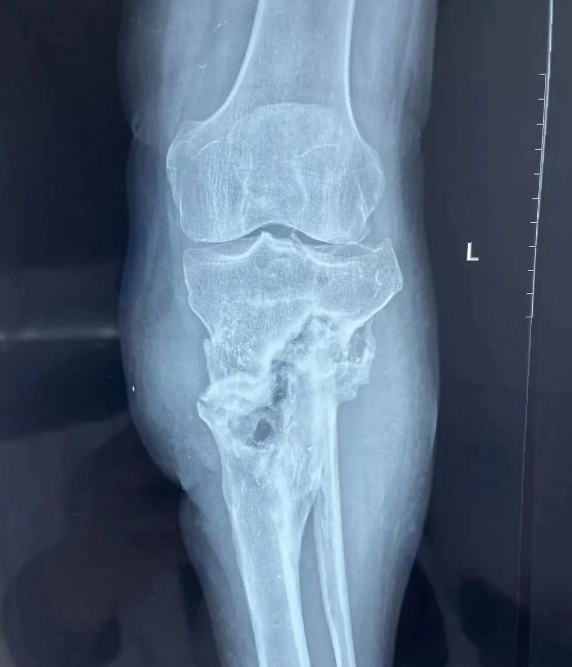

首先接待马先生的是该院胫踝科的医生黄煜,经过询问和检查,确诊为左侧胫腓骨近端均有慢性骨髓炎(业界称其为不死的“癌症”)病灶,死骨长度10余厘米,皮肤溃疡并死骨外露,保肢难度很大。听闻此言,当时马先生和家人心底掠过阵阵寒意。

准备周全后,手术如期进行,吴慧敏、蒋君齐上场,手术分两期完成。一期先行清创、去除死骨,二期行皮瓣、肌瓣覆盖。吴慧敏作为主刀,从伤口内层层包裹的骨痂中取出沉积于此数十年的沙砾等,彻底去除死骨,清理死腔这一罪魁祸首。二期于临近春节时进行,后经医护团队精心治疗护理,伤口逐渐愈合,已拆线。